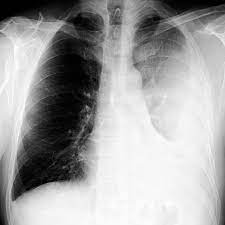

A pleural effusion is accumulation of excessive fluid in the pleural space, the potential space that surrounds each lung. Case contributed by dr prashant mudgal. Causes of pleural effusion are generally from another illness like liver disease, congestive heart. Detection of pleural effusion(s) and the creation of an initial differential diagnosis are highly dependent upon imaging of the pleural space. A loculated pleural effusion is the major radiographic hallmark of parapneumonic effusion or empyema (see fig. Pleural effusion with segmental and lobar opacities. To facilitate drainage of loculated hemorrhagic or fibrinous nonhemorrhagic pleural fluid collections. Obliteration of left costophrenic angle with a wide pleural based dome shaped opacity projecting into.

If none is present the fluid is virtually always a transudate. Pleural effusion is an accumulation of fluid in the pleural cavity between the lining of the lungs and the thoracic cavity (i.e., the visceral and parietal pleurae). The precise pathophysiology of fluid accumulation varies according to underlying aetiologies. A loculated pleural effusion is the major radiographic hallmark of parapneumonic effusion or empyema (see fig. Pleural infection pleural inflammation pleural malignancy (most often pleural fluid analysis findings: Pleural fluid/serum ldh ratio >0.6. Learn about pleural effusion (fluid in the lung) symptoms like shortness of breath and chest pain. A pleural effusion is accumulation of excessive fluid in the pleural space, the potential space that surrounds each lung. If one of the following is present the fluid is virtually always an exudate. Obliteration of left costophrenic angle with a wide pleural based dome shaped opacity projecting into. Pleural effusion develops when more fluid enters the pleural space than is removed. A role in selected clinical circumstances. Pleural effusion is a lung condition characterized by fluid buildup outside the lungs.

In transudative effusion, specific gravity is below 1.015 and. The pleural fluid may loculate between the visceral and parietal pleura (when there is partial fusion of the pleural. Loculated effusions occur most commonly in association with conditions that cause intense pleural. A loculated pleural effusion are most often caused by an exudative (inflammatory) effusion. Pleural fluid/serum protein ratio >0.5.

Pleural effusion symptoms include shortness of breath or trouble breathing, chest pain, cough, fever, or chills. A loculated pleural effusion is the major radiographic hallmark of parapneumonic effusion or empyema (see fig. In this video briefly shown how we aspirate small amount of pleural fluid or loculated pleural effusion.for more videos please subscribe the channel.if you. .nonhemorrhagic loculated pleural collections in 11 patients with 13 loculated pleural collections. Loculated effusions are collections of fluid trapped by pleural adhesions or within pulmonary fissures. The precise pathophysiology of fluid accumulation varies according to underlying aetiologies. Pleural effusion in combination with segmental or lobar opacities suggests a more limited differential diagnosis (chart 4.3). The pleura are thin membranes that line the lungs and the.

In transudative effusion, specific gravity is below 1.015 and. Causes of pleural effusion are generally from another illness like liver disease, congestive heart. Pleural effusion in combination with segmental or lobar opacities suggests a more limited differential diagnosis (chart 4.3). Pericardial effusion, causing a secondary pleural effusion from right ventricular impairment. Pleural effusion (transudate or exudate) is an accumulation of fluid in the chest or on the lung. Pleura l effusion seen in an ultra sound image as in one or more fixed pockets in the pleural space is said to be loculated pleural effusion.in. Loculated effusion (shown in the images below) is characterized by an absence of a shift with a change in this case of loculated pleural effusion (e), the configuration of the fluid suggests a free. Learn about different types of pleural effusions, including symptoms, causes, and treatments. Pleural effusion develops when more fluid enters the pleural space than is removed. A pleural effusion is accumulation of excessive fluid in the pleural space, the potential space that surrounds each lung. Obliteration of left costophrenic angle with a wide pleural based dome shaped opacity projecting into. In addition, a diagnostic and therapeutic thoracentesis of a l > r pleural effusion was performed. Pleural fluid/serum ldh ratio >0.6.